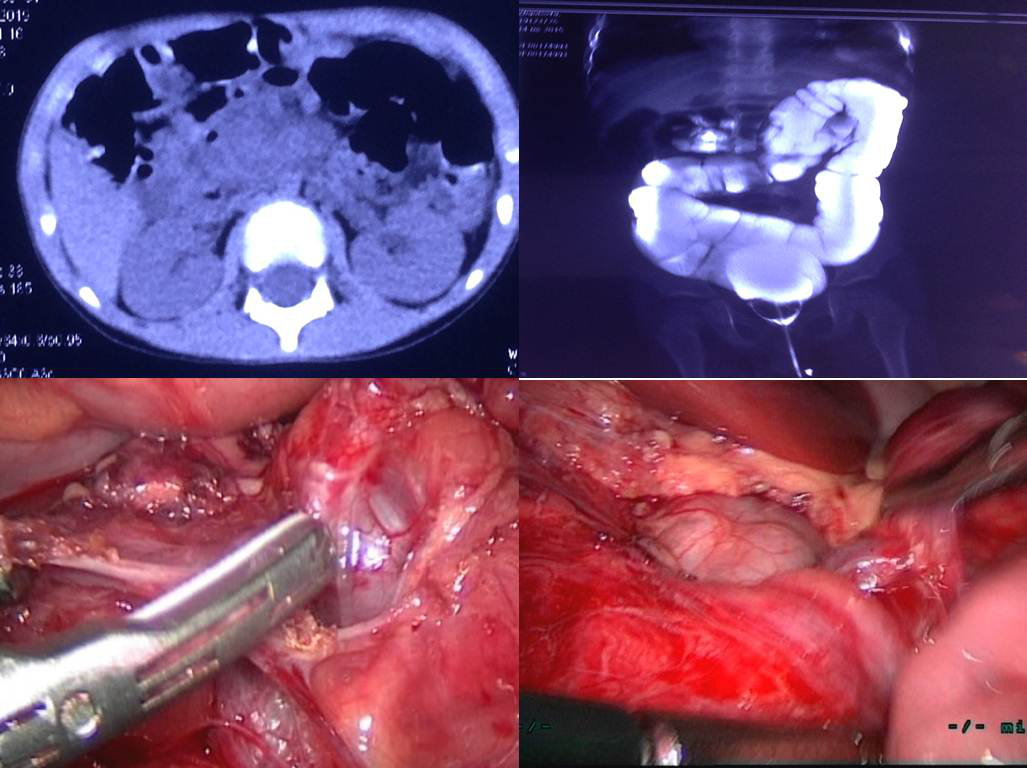

【本站讯】近日,小儿外科崔新海教授、副主任孙丰银教授团队与麻醉科、NICU协作完成第3例新生儿腹腔镜Ladds术治疗肠旋转不良,手术时间约82分钟,患儿术后恢复良好,已顺利出院,正密切随访中。

肠旋转不良的发病率约0.2%,85%有症状患儿发生于新生儿期。新生儿体腔小,心血管功能不稳定,肺功能不完善,多数患儿为早产低体重,耐受力差,进一步加大了手术难度,因此手术团队必须具备高超的手术技巧和丰富的临床经验。新生儿手术涉及麻醉、NICU协作,每次术前孙丰银教授都做了充分的协调准备工作,跟麻醉科张鹏教授协商麻醉注意事项,联系NICU预留床位,预防术后出现需要呼吸机支持等情况。

腹腔镜Ladds术

该手术团队成员还包括陈嘉伟主治医师、李国伟主治医师、陈鲁秋医师,手术团队在积累了上千例三四级手术基础上,从18年开展新生儿腹腔镜手术,利用传统5mm腔镜器械,先易后难,首先开展了幽门肌层切开,逐步开展复杂十二指肠菱形吻合术、Ladds术等。团队累计完成幽门肌层切除术13例、Ladds术3例、食管闭锁2例、环状胰腺十二指梗阻3例、膈疝2例、无肛2例,手术技巧、经验不断完善,已成为科室常规手术。

通过腹腔镜技术,可明确诊断病变部位,避免传统开刀大切口及探查困难后延长刀口带来的创伤,术后具有肠功能恢复早、痛苦小、切口小且美观、住院时间短、并发症减少等优点。绿帽社 小儿外科新生儿腹腔镜手术技术已迈上新台阶,在省内充分发挥了辐射引领作用,弥补了此技术在省内医疗机构开展较少的缺憾,将竭力为省内及全国患儿提供更优质的微创治疗。